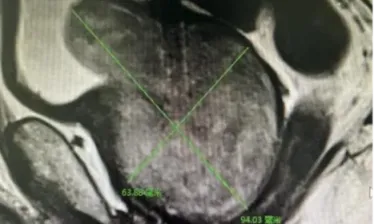

- 年轻女性深藏“刺客”,宝鸡市中心医院港务院区脊柱骨病矫形骨科...